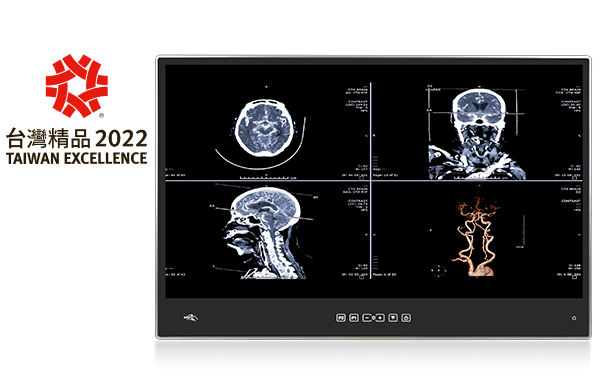

Medical Computer

IEI has long been committed to developing high-quality products for medical industry to facilitate healthcare delivery. With the other’s interest in mind, IEI will continue to make contribution to creating a good working environment for medical personnel and a better medical service for patients.